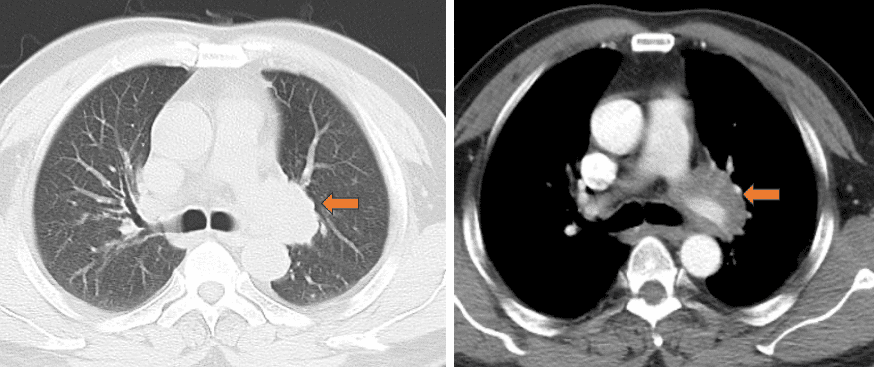

胸部CT(2017-05-10 我院)示 左肺门占位 ,考虑恶性可能性大,建议支气管镜检查;纵隔淋巴结肿大;双侧胸膜局限性增厚、钙化。